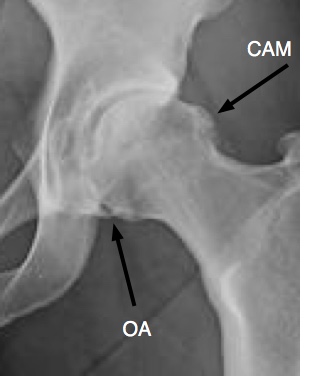

You may well have what we call an impingement syndrome in the hip; then it becomes stiff and painful, may click and getting in and our of a chair, or the car becomes difficult; and, if you don't exercise it, it becomes arthritic.